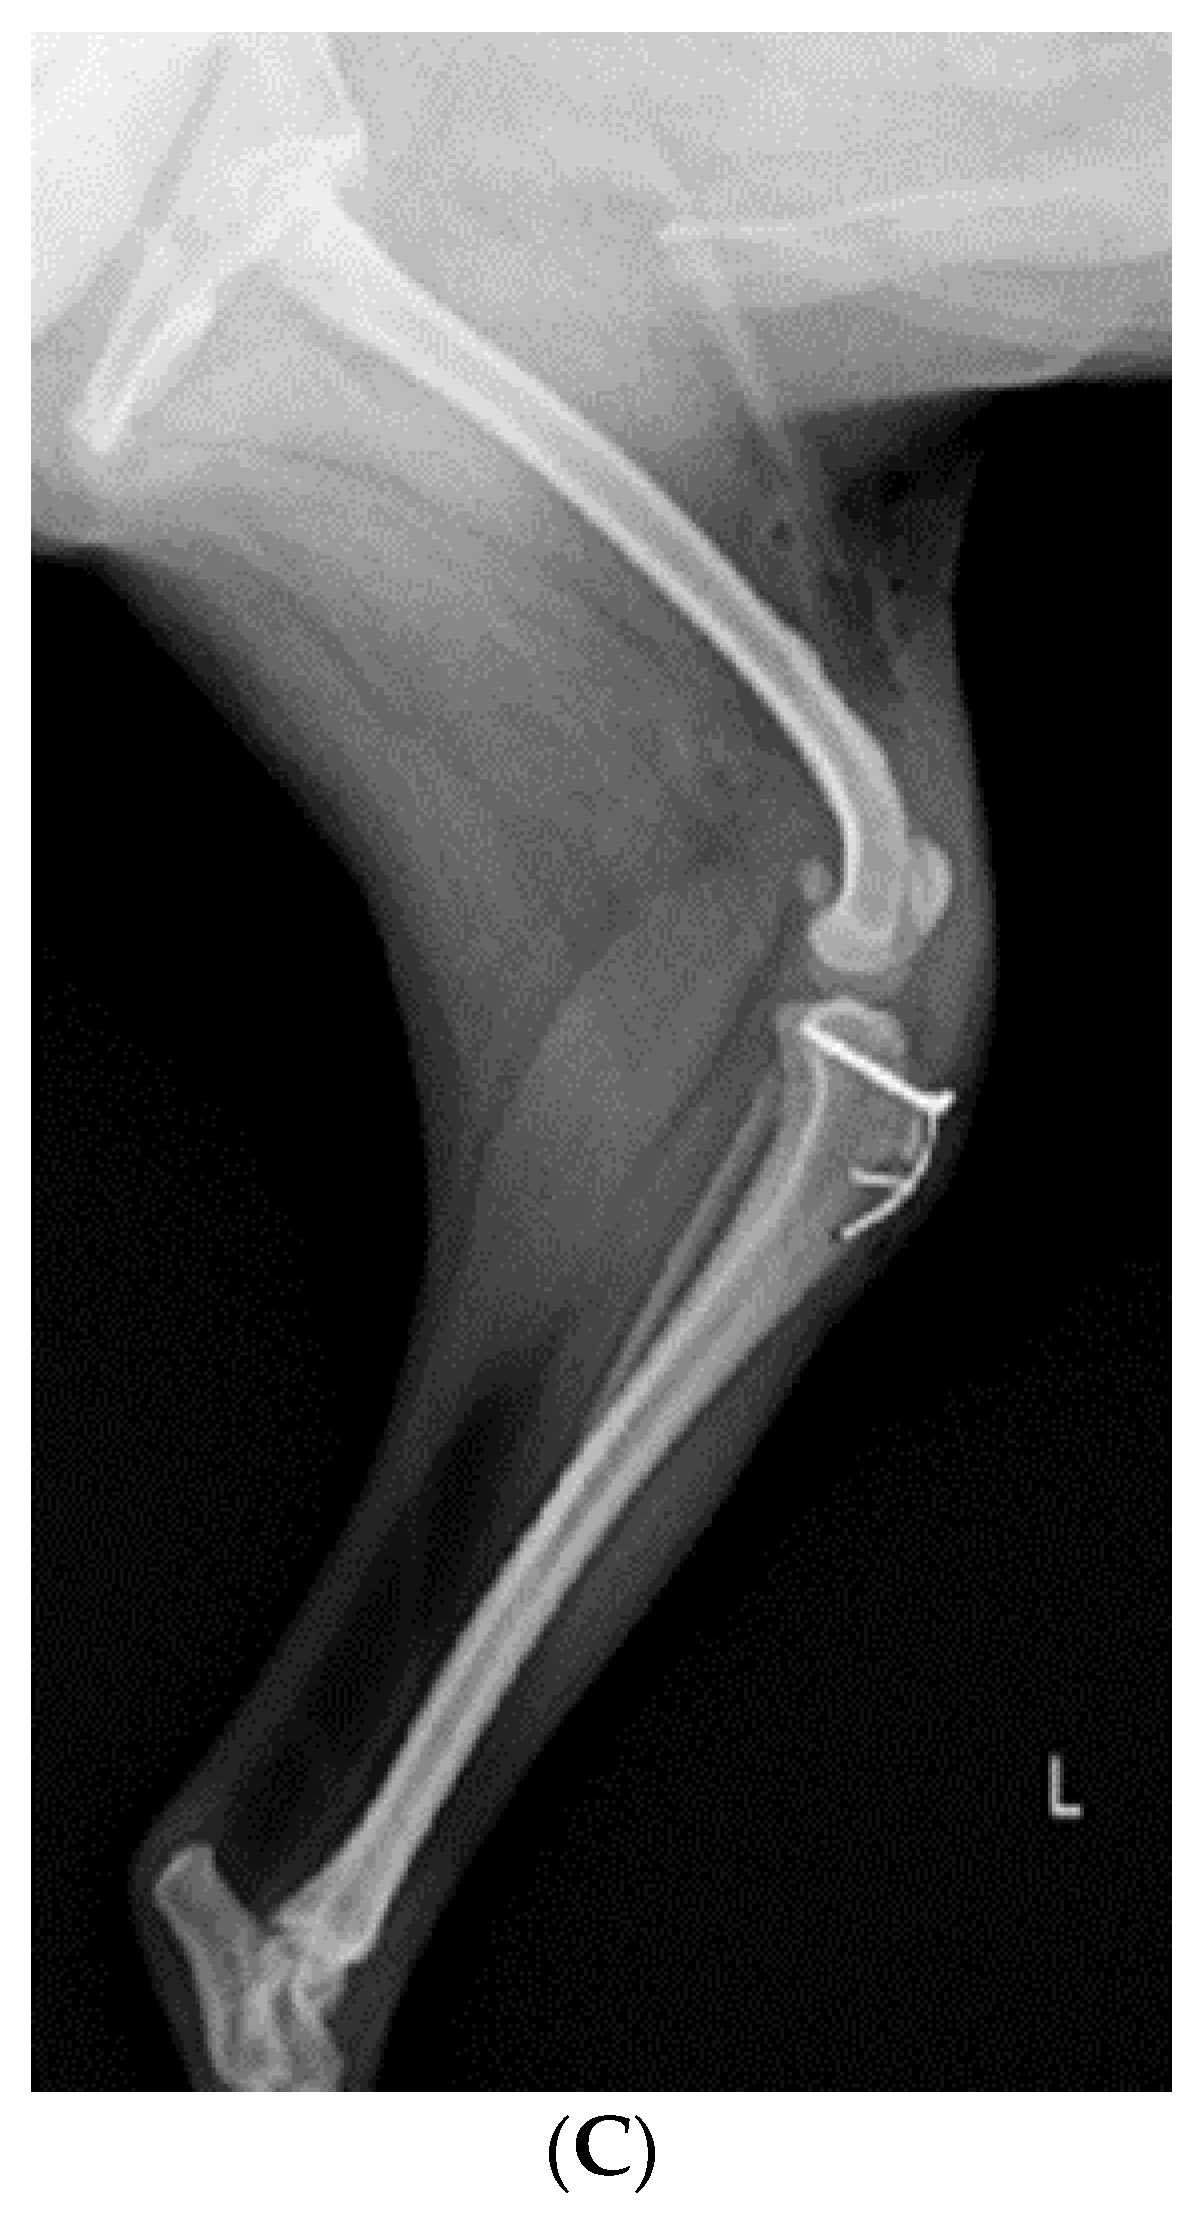

Figure 4.

Radiograph images depicting the stifle joint arthrodesis performed on the right hind limbs and the medial patellar luxation correction of the left hind leg. (A) Craniocaudal radiographic view of both stifle joints. (B) Mediolateral radiographic view of stifle joints following SJA. (C) Postoperative mediolateral view of MPL in the left hindlimb.

2.4. Reconstruction of MPL

After performing SJA of the right hind limb, MPL correction of the left hind limb was performed. The approach was carried out by making a vertical incision of about 10 cm in the craniolateral parts around the stifle joint. After the fascia and articular capsule were incised to expose the trochlea of the femur, tracheoplasty was performed in a wedge shape to secure the depth of the trochlea. Then, the wedge-shaped articular cartilage was inserted into the femoral trochlea. Subsequently, a tibial tuberosity that had moved toward the inside was cut using a bone saw and moved laterally to fit the patella into the trochlear groove using a K-wire (Figure 4A,C). Stability was further enhanced using the figure-of-eight-tension-band-wiring technique. Before suturing, the distal tibia was rotated internally and externally 2–3 times to confirm that the patella (Figure 4A,C) remained stable in the newly formed trochlear groove. Subsequently, routine closure was performed in the following order: joint capsule, muscle, subcutaneous tissue, and skin.